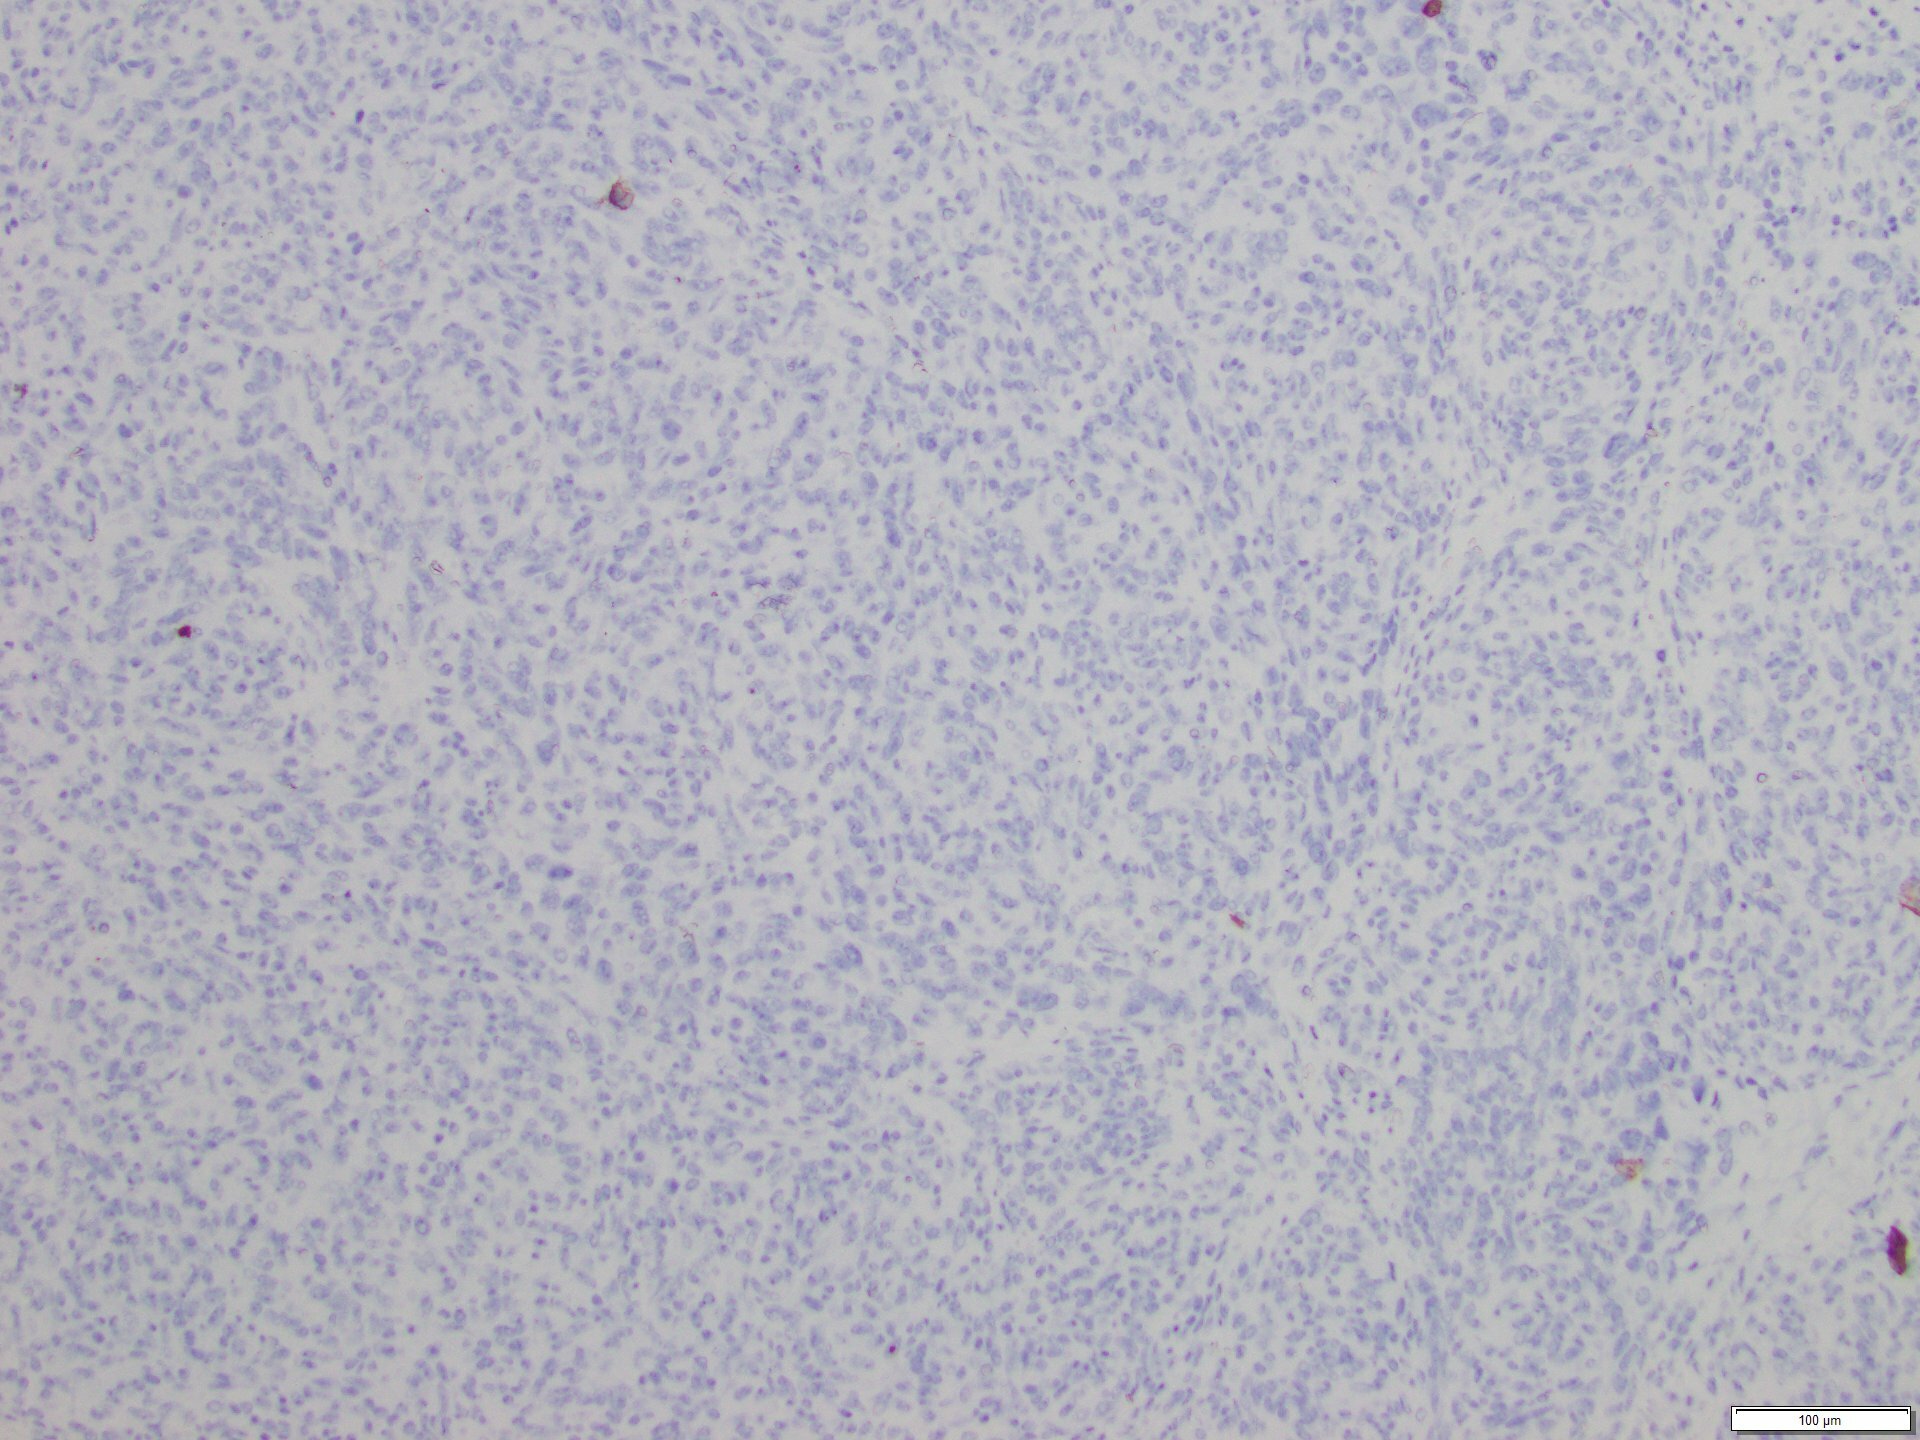

The skin lesion was completely excised and sent to pathology for diagnosis (Figures 1-3). The lesion is hypercellular with an infiltrative, predominantly solid, growth pattern in the dermis and subcutaneous tissue. It is highly vascular and has complex anastomosing and poorly formed vascular channels. The tumor cells are large, pleomorphic, have vesicular chromatin, and prominent nucleoli. There are frequent mitoses and extravasated red blood cells throughout. Immunohistochemistry shows the tumor cells are diffusely positive for ERG (Figure 4) and c-MYC (Figure 5) while negative for pan-cytokeratin (Figure 6) and GATA3. Subsequently, the patient underwent a left total mastectomy.